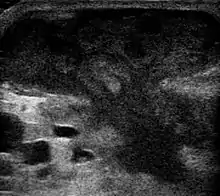

![]() | |

| Five-day-old inflamed epidermal inclusion cyst. The black spot is a keratin plug which connects with the underlying cyst. | |